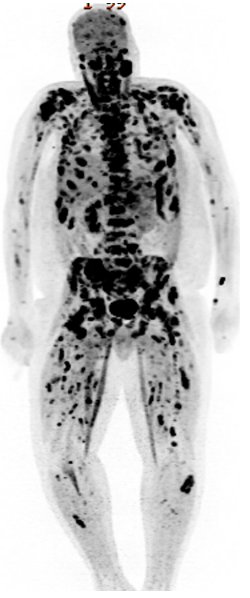

A 40-year-old Hispanic male presented to the emergency department with complaints of back pain for 3 weeks. He described the pain as aching and circumferential involving the sternum, right ribs, shoulders, and back. His previous medical history was unremarkable and he never had any prior imaging studies. Plain radiographs of the spine did not show any osseous abnormalities. Because of the patient’s highly elevated alkaline phosphatase (1,051 IU/L), a computed tomography (CT) scan of the chest, abdomen, and pelvis was performed (Figure 1). This revealed an enhancing right upper pole renal mass suspicious for renal cell carcinoma with nodal, left adrenal and extensive bony metastasis. In the chest, there were extensive lytic and sclerotic bone metastases. Interventional Radiology performed a CT guided core biopsy of one of the metastatic lesions in the left iliac crest; cytology reported metastatic malignant cells with immunohistochemical findings positive for Ae1/Ae3 and PAX8. This was highly suggestive of metastatic renal cell carcinoma, however, the specific histological subtype (clear cell vs non-clear cell) was not identified due to an insufficient tissue sample from the earlier core biopsy. A subsequent positron emission tomography (PET) scan revealed extensive metastases with multiple soft tissue implants, retroperitoneal lymph nodes and extensive osseous involvement (Figure 2). The patient was scheduled for a repeat core biopsy (retroperitoneal) for a more specific histological diagnosis (clear cell vs nonclear cell) on the demand of the treating oncologist and commenced on treatment with Sunitinib in the interim. This is in accordance with the National Comprehensive Cancer Network (NCCN) guidelines, which recommends sunitinib as the first-line (category 1) therapy for both clear cell and non-clear cell stage IV renal cell carcinoma. He was also prescribed opioid analgesics, anti-emetics and laxatives. The treating oncologist planned to switch the patient over to immunotherapy with nivolumab or ipilimumab if the repeat core biopsy revealed that he had the clear cell histological subtype. Unfortunately, the patient’s health progressively deteriorated, he was unable to attend hospital appointments and finally passed away about 2 months from his initial presentation.

Figure 2: Positron emission tomography (PET) scan showing extensive osseous metastasis.